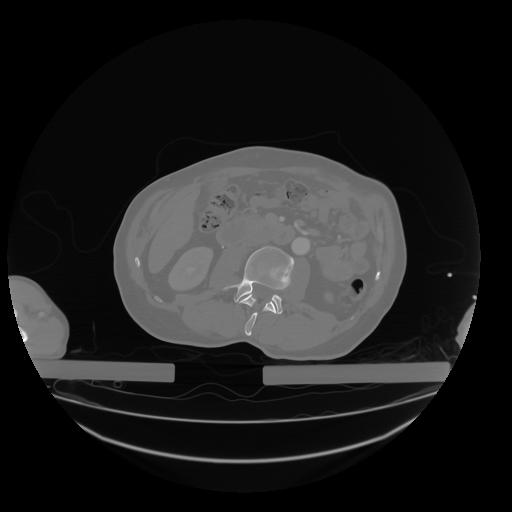

28 CUERPO,CE,Vol,2.0,CUERPO,,